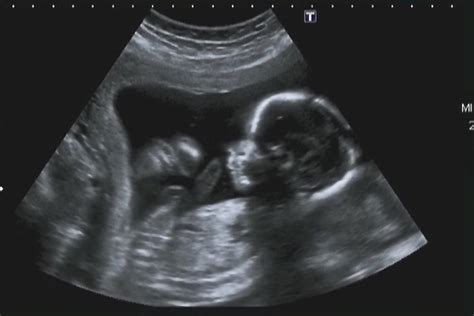

Kaip rodo ultragarso duomenys, kūdikis pradeda judėti labai anksti, 7-8 nėštumo savaitę, bet būsimoji mama šių judesių dar nejaučia. Tiesiog šių judesių mama pati niekaip dar negali jausti, ir jie gali būti matomi tik atliekant ultragarso tyrimą.

Gyvendamas mamos pilvelyje kūdikis tam tikrus judesius atlieka jau nuo antro nėštumo mėnesio. Pirmuosius judesius, kurie dar nejaučiami mamai, puikiai galima matyti darant ultragarso procedūrą. Tuo tarpu juos pajaučia moterys įvairiu nėštumo laiku. Pirmą kartą gimdančios dažniausiai šiek tiek vėliau už antrą kartą ir daugiau gimdančiąsias.